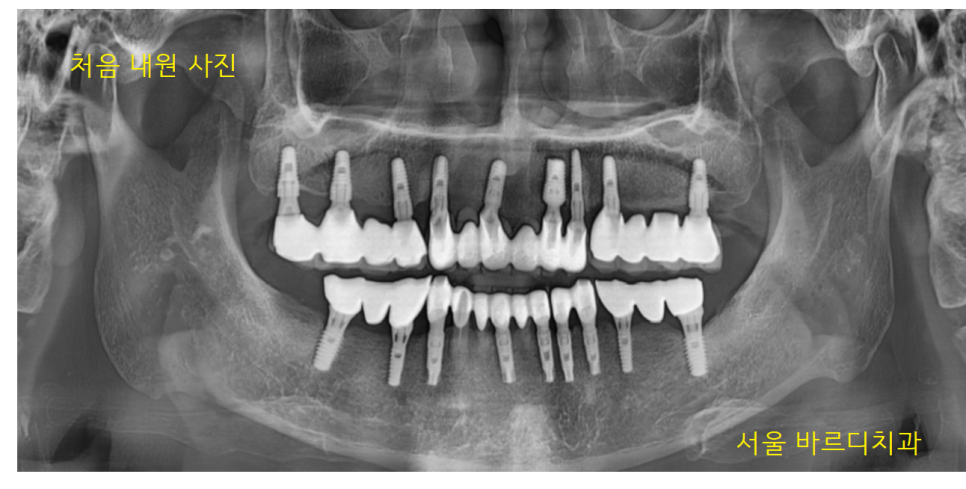

처음 내원은 2023.04.14이었습니다.

23.04.14

왼쪽 아래 보철물이 빠져서 내원하셨고

보철을 다시 붙여주는 것으로 치료를 마무리

오신 김에 다른 부위도 같이 검진해 드렸는데요

겉으로 보기에도 보철이 깨지고

오래된 흔적들이 보이네요~